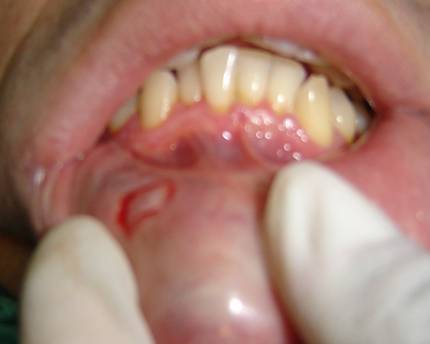

I. Hola JMendoza, tengo entendido que estos puntos blancos en la zona que menciona suelen tratarse de una infección bacteriana o bien causada por hongos.. en estos casos creo que suelen denominarse aftas bucales.

Como bien ha dicho, puede deberse también a una obstrucción/inflamación de una glándula salivar menor, aunque esta opción la desconozco en gran medida, pienso que por extensión existen una serie de problemas que son generados a patir de esta inflamación de la glándula, como por ejemplo son Mucocele

He leído sobre otro cuadro llamado ''Milia'', que consiste en pequeñas protuberancias blancas (quistes) que aparecen cuando una serie de células muertas quedan atrapadas en la piel. Suelen aparecer en la cara, aunque es frecuente ver algunas en los labios. No encuentro imágenes especificas de la zona labial pero puede ver estos tutoriales por si se correspondiese,